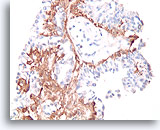

Papilloom, Borst FNA, Celblok.

Immunokleuring met p63 van de coupes van de patiënt in afbeelding 23-25 helpt de myoepitheliale cellen te markeren die door deze papilloom verstrooid zijn.

10X

Papilloom, Borst FNA, Celblok.

Immunokleuring met p63 van de coupes van de patiënt in afbeelding 23-25 helpt de myoepitheliale cellen te markeren die door deze papilloom verstrooid zijn.

10X

Papilloom, Borst FNA, Celblok.

De myoepitheliale cellen vormen nagenoeg continue rijen onder de ductale cellen (immunokleuring met p63).

40X

Papilloom, Borst FNA, Celblok.

De myoepitheliale cellen vormen nagenoeg continue rijen onder de ductale cellen (immunokleuring met p63).

40X